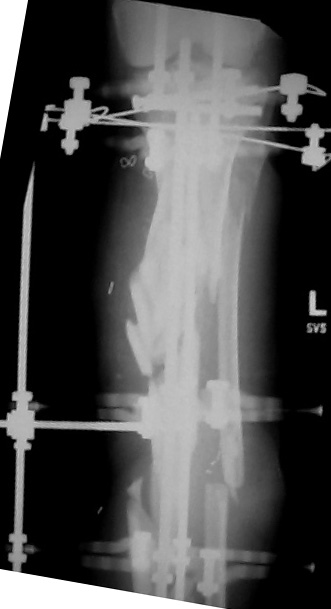

I would appreciate treatment suggestions.My patient is a 30 year old with a very comminuted tibia fracture 6 weeks ago.It was grade 3B open. Initial treatment included irrigation, debridementClick images to enlarge.

and a hybrid external fixator including femur, tibia and foot. Screwswere placed in the plateau and plafond and a free flap plus STSG. Theskin is ok but atrophic. The femoral pins were removed and knee motionstarted at 6 weeks. There is no sign of callus. There is one pin inthe one large fragment of the diaphysis. All the pieces are lined upreasonably well. The XF pins are ok. Suggestions? Thank you.